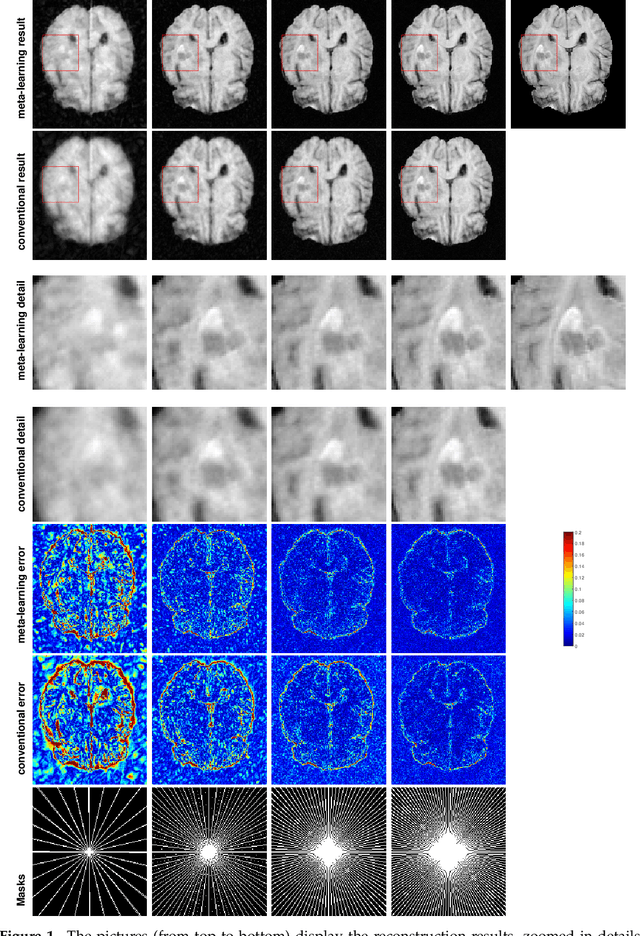

Abstract:Purpose: This work aims at developing a generalizable MRI reconstruction model in the meta-learning framework. The standard benchmarks in meta-learning are challenged by learning on diverse task distributions. The proposed network learns the regularization function in a variational model and reconstructs MR images with various under-sampling ratios or patterns that may or may not be seen in the training data by leveraging a heterogeneous dataset. Methods: We propose an unrolling network induced by learnable optimization algorithms (LOA) for solving our nonconvex nonsmooth variational model for MRI reconstruction. In this model, the learnable regularization function contains a task-invariant common feature encoder and task-specific learner represented by a shallow network. To train the network we split the training data into two parts: training and validation, and introduce a bilevel optimization algorithm. The lower-level optimization trains task-invariant parameters for the feature encoder with fixed parameters of the task-specific learner on the training dataset, and the upper-level optimizes the parameters of the task-specific learner on the validation dataset. Results: The average PSNR increases significantly compared to the network trained through conventional supervised learning on the seen CS ratios. We test the result of quick adaption on the unseen tasks after meta-training and in the meanwhile saving half of the training time; Conclusion: We proposed a meta-learning framework consisting of the base network architecture, design of regularization, and bi-level optimization-based training. The network inherits the convergence property of the LOA and interpretation of the variational model. The generalization ability is improved by the designated regularization and bilevel optimization-based training algorithm.